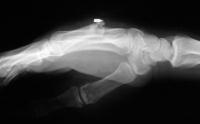

The injury: point blank handgun injury, palmar to dorsal through the middle metacarpal. Contusion of the third web space common digital nerve.

The treating surgeon debrided the wound and maintained length with intermetacarpal pins. When the wound was stable, the fracture was treated with bone graft, plate and screws.